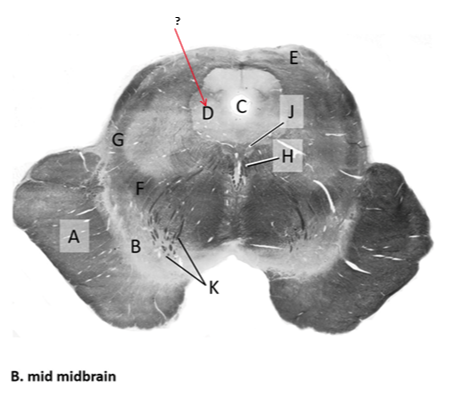

Name this and state its function.

Tectum.

Name this and its divisions+ function?

Substantia nigra.

Cerebral aqueduct.

Crus cerebri.

Medial Lemniscus.

Name this, what is it and state its function.

Lateral lemniscus.

Name this, state its function[2 marks] and how it goes about its function[4 marks].

Medial longitudinal lemniscus.

How?

Oculomotor nucleus.

Name this, state its function[3 marks] and cells involved contributing to function.

Periaqueductal grey.

Root fibres of Oculomotor nerves(CN III).